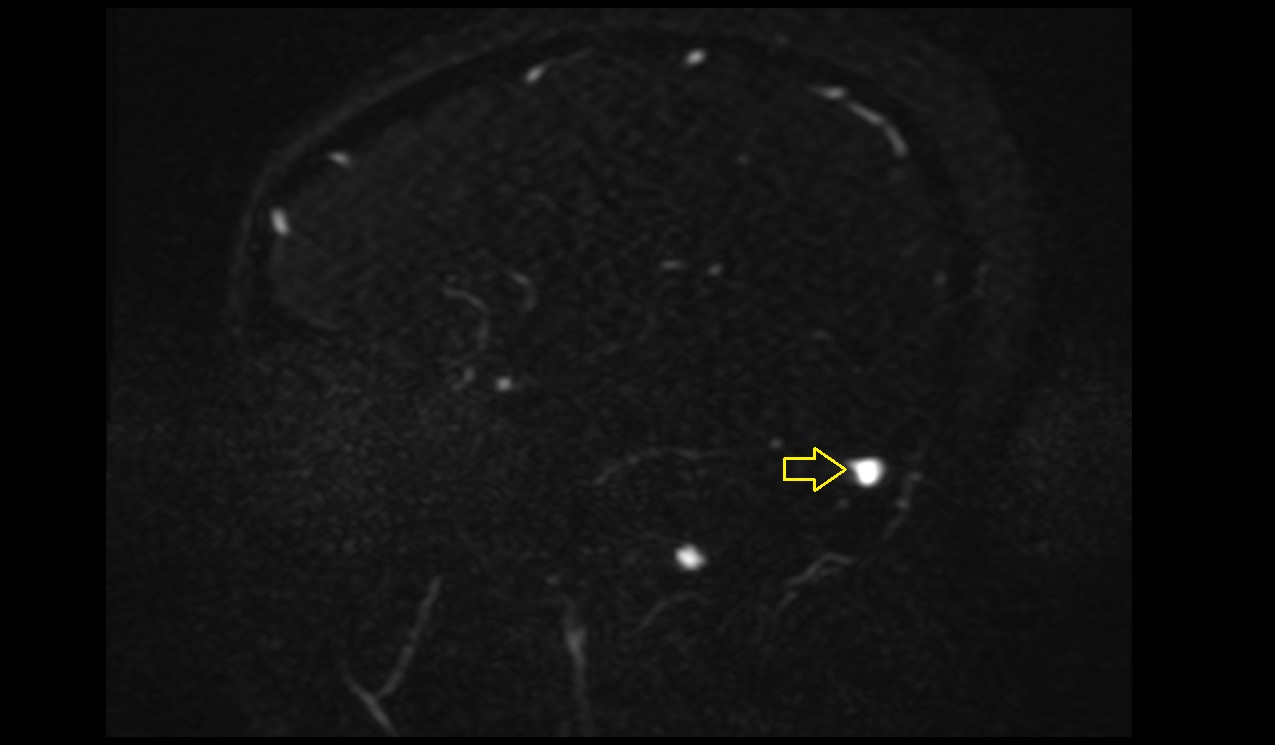

- Anterior hippocampal veins

- Choroid plexus